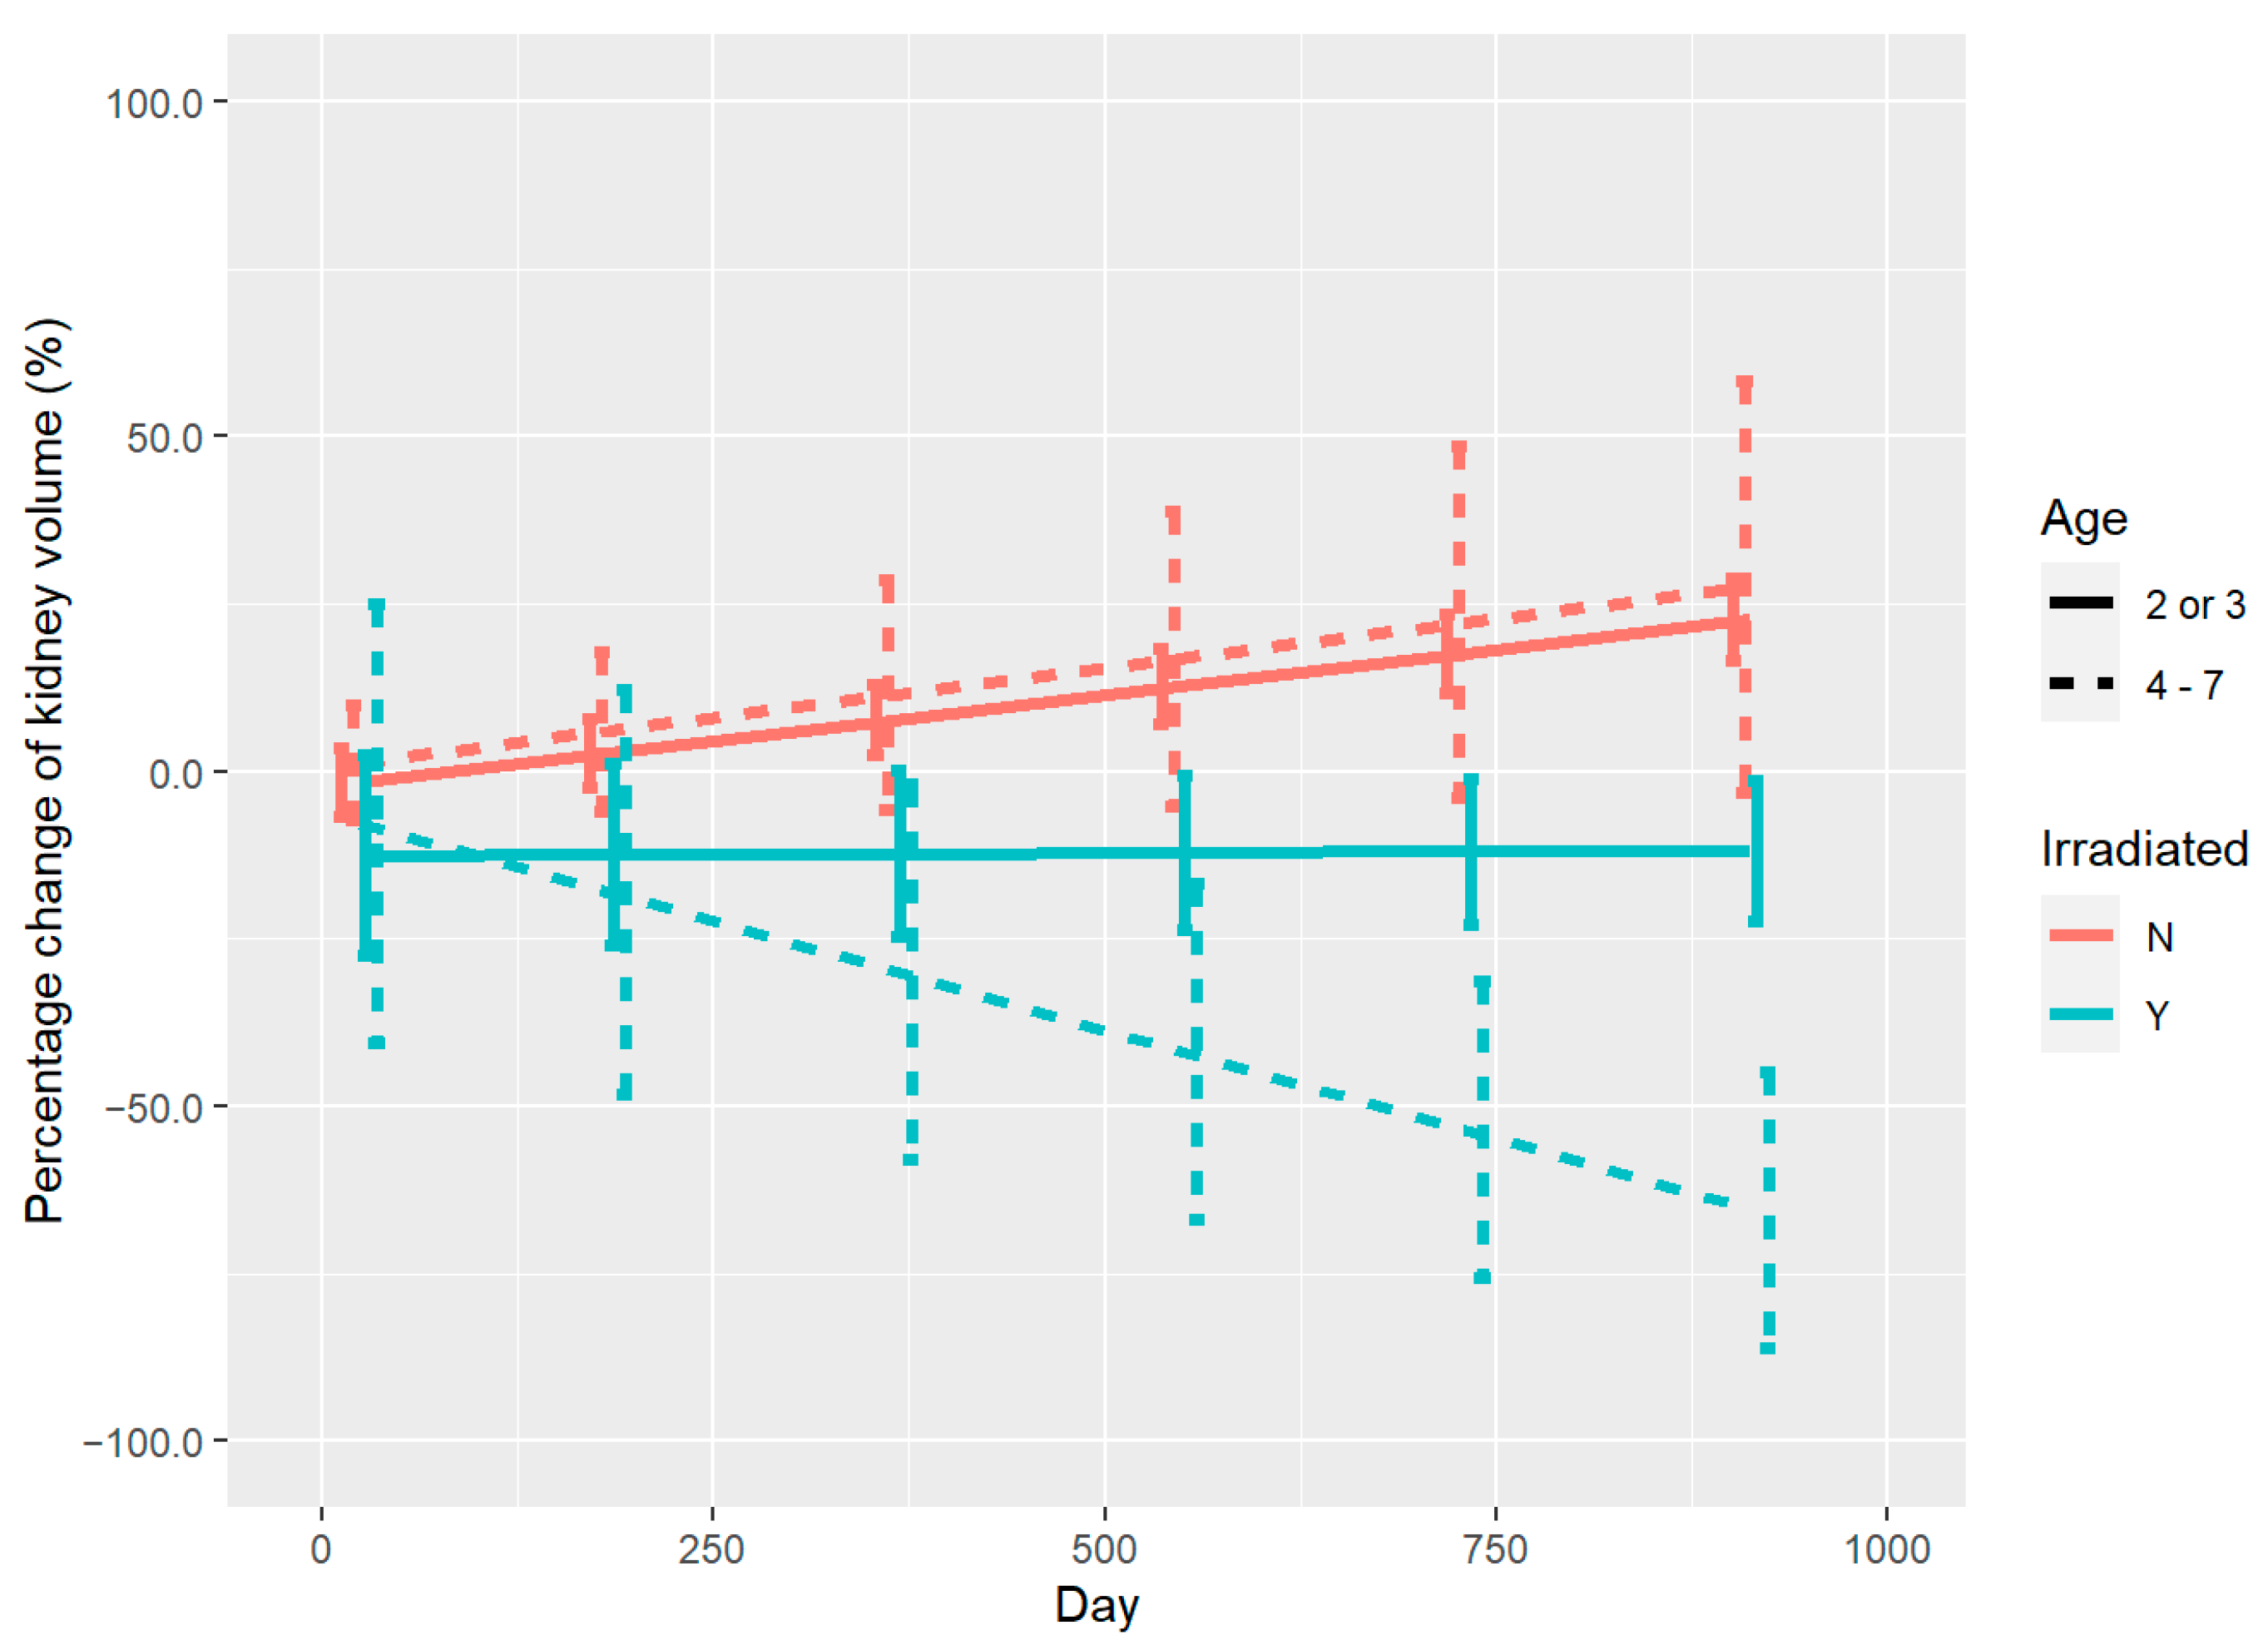

3.2. Renal Volume Changes and DVH Analysis